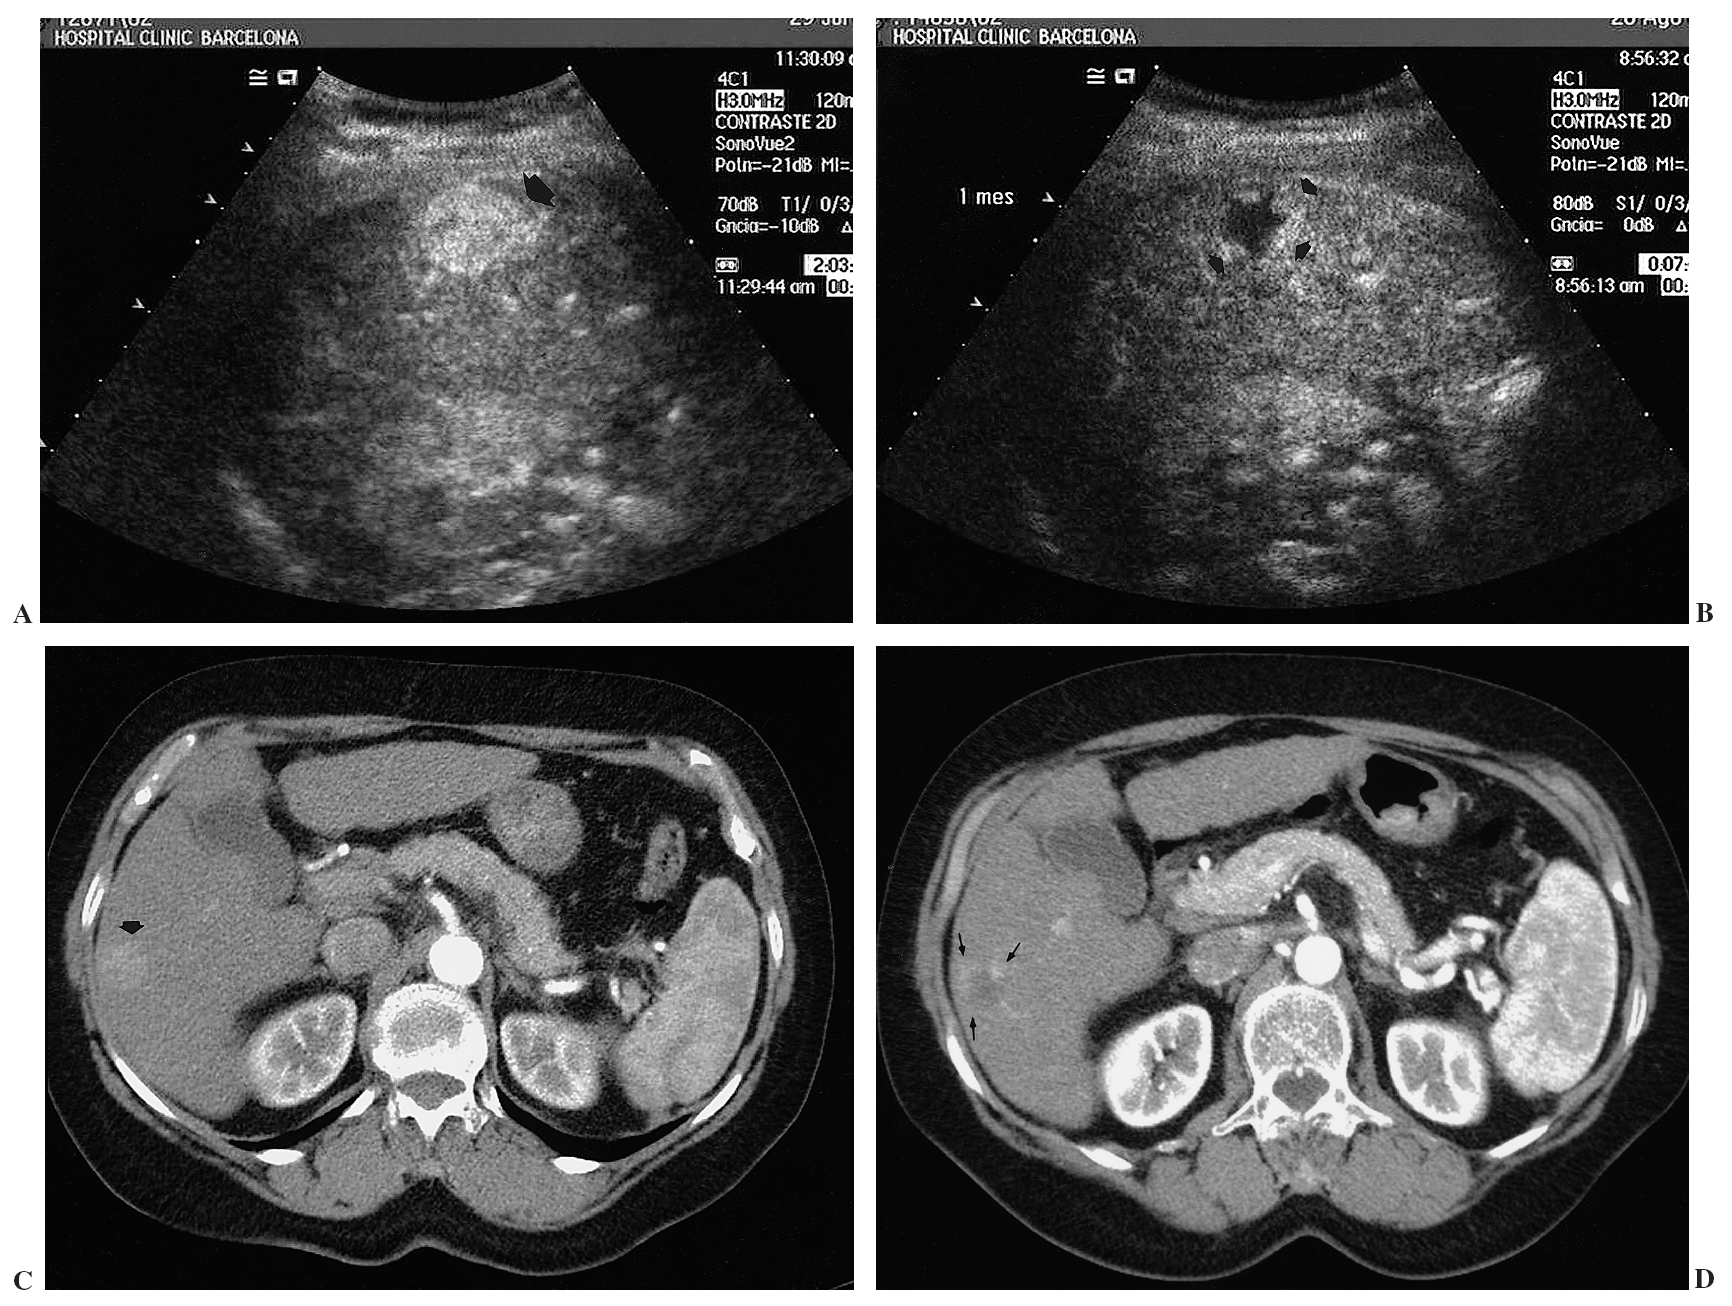

Contraste en ecografía.

Permite mejorar el diagnóstico en diferentes patologías. En un principio se usaba para distinguir entre patología tumoral hepática benigna o maligna, pero actualmente esta tecnica se ha ampliado. Se usan como medio de contraste microburbujas encapsuladas o partículas sólidas